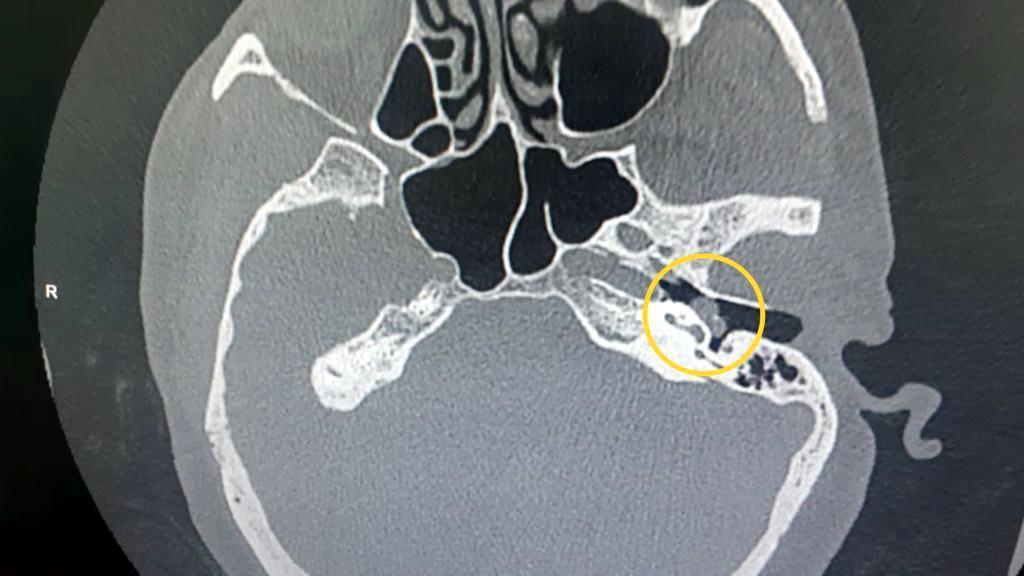

Balıkesir İvrindi Devlet Hastanesi'nde görevli hemşire Nazlı Kurt, işitme kaybı nedeniyle başvurduğu hastanede yapılan tetkiklerde kulak kemiğinde 'glomus timpanikum' tümörü tespit edildi. Büyümesi durumunda hastanın hayatını tehlikeye sokan tümörün tedavisi için araştırma yapan Kurt, Zonguldak Bülent Ecevit Üniversitesi Tıp Fakültesi Cerrahi Tıp Bilimleri Kulak Burun Boğaz Hastalıkları Öğretim Üyesi Dr. Deniz Baklacı'ya ulaştı. Geçen 22 Haziran'da aynı hastalıkla ilgili Ayten Aydın'ı (56) ameliyat ederek sağlığına kavuşturan Dr. Baklacı ve ekibi, hemşire Kurt'un tedavisine de başladı. Kurt, 3 saat süren ameliyatla sağlığına kavuştu.

"Bizim hastamızda şikayet kulaktaki nabız sesi ve işitme kaybıydı. Bu şekilde dış merkezdeki bir klinikte tanısını almış bir hasta. Ardından tarafımıza başvurdu. Biz gerekli tetkiklerle bu tanıyı doğruladık ve bunun için cerrahi müdahaleyi önerdik. 3-3,5 saatlik bir cerrahiydi. Orta kulaktan tamamen temizledik tümörü. Kapalı olarak yapıldı ameliyat. Bu bizim için ikinci bir vakaydı. Hastamız şu an gayet iyi. Geçmiş olsun."